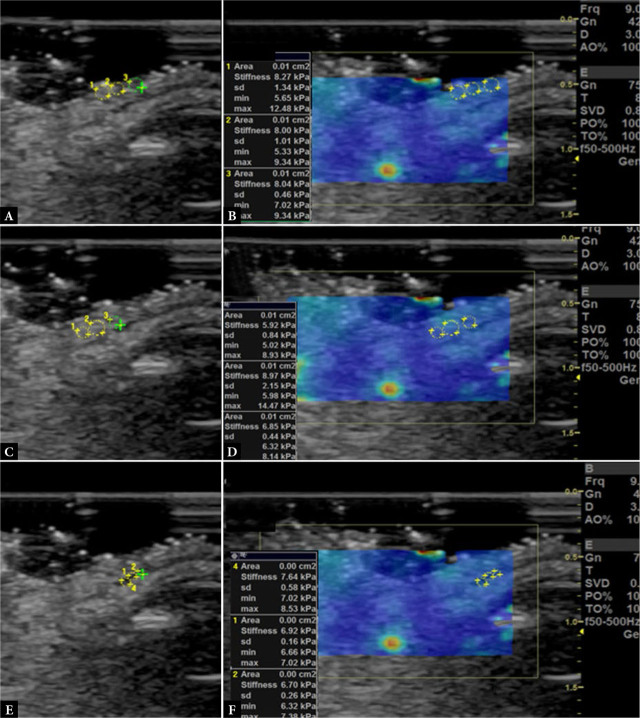

Methods: This is a prospective case-control study. Patients were recruited from the Oculoplastic Service of the Department of Ophthalmology at the University Hospital of Heraklion, Crete, Greece. The diagnosis of floppy eyelid syndrome was based on the eversion of the upper eyelid upon unassisted digital traction. Cataract surgery candidates without floppy eyelid syndrome were consecutively recruited as controls. Patients with a history of previous eyelid pathology or surgery were excluded. Ultrasound examination was performed using high-frequency linear probes (GE E9) for B-mode imaging and shear wave and strain elastography. Upper airway measurements included tongue thickness and upper airway length. Clinical and demographic findings were recorded.

Results: Twenty-eight patients were included (14 with floppy eyelid syndrome, 14 controls). Orbicularis muscle elasticity in kPa was significantly higher in the floppy eyelid syndrome group, compared with controls (independent samples t-test score 2.64, p = 0.04). Tongue thickness and upper airway length were also significantly correlated with several eyelid B-mode and elastography parameters in patients with floppy eyelid syndrome, including subcutaneous fat and orbicularis muscle thickness and elasticity.